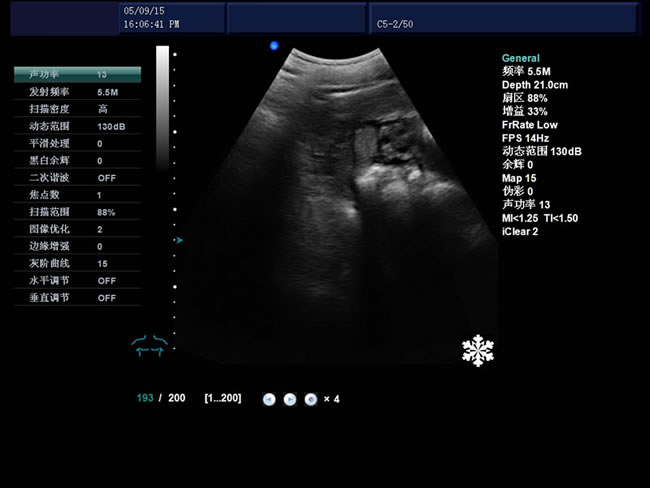

S8 彩色多普勒獸用超聲診斷儀

• S8彩色多普勒獸用超聲診斷儀是徐州市大為電子設備有限公司推出的一款全新的彩色超聲診斷儀器。

探頭信息、顯示模式、深度、焦點、動態范圍、體標、探頭位置標志、聲功率、患者信息、醫療機構名稱、測量值、時間和日期、標尺、掃描方向、灰階曲線、探頭當前工作

頻率、幀頻、B模式總增益、C模式總增益、D模式總增益、菜單、注釋、灰階帶、穿刺引導線、PRF、壁濾波、血流相關、累積次數、TI熱指數、MI機械指數